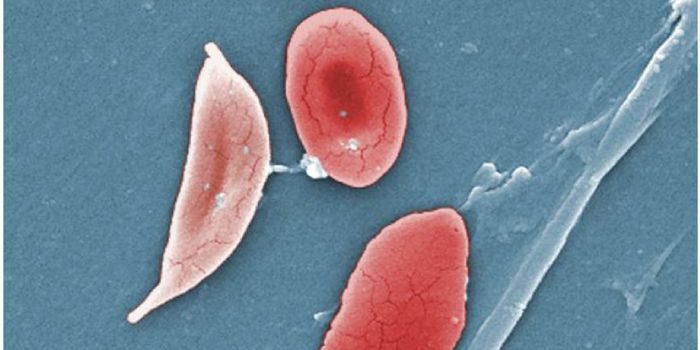

MAR 26, 2017Clinical & Molecular DXLab-grown red blood cells are not a new concept. But culturing enough of these cells in mass quantities was the main cha ...